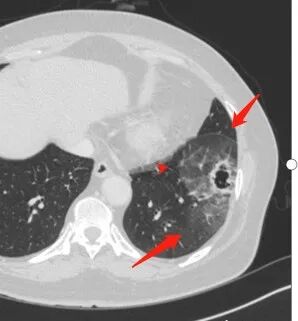

1、左肺下叶外基底段不规则囊腔样病灶,囊腔内有条形影及血管穿行。

2、囊壁薄厚不均匀,稍显僵硬,有壁结节(对应边缘分叶等)、结节强化明显。

以上两条几乎将肺囊肿彻底排除在外,且高度怀疑新生物!

3、灶周环以大范围磨玻璃影,非常均匀,没有重力分布趋势,分叶状,边界隐约可变。

4、冠状位部分层面可见支气管在囊腔边缘截断。

囊腔有张力,外形有分叶,壁厚薄不均,有间隔,有强化

胸CT:左肺下叶囊腔,壁厚薄不均,可见壁结节,囊腔内可见断裂小梁,部分融合,周围边界较清楚GGO,胸膜牵拉,可见血管集束、支气管充气征,冠状位部分层面可见支气管在囊腔边缘截断。考虑:囊腔型腺Ca。鉴别:肺大疱感染,CPAM等。

本例囊腔性病灶尽管腔壁稍显僵硬,壁结节凸显,但女性患者,灶周明显磨玻璃晕,都强烈提示为囊腔性腺癌。

大范围磨玻璃影可以符合粘液腺癌。机制包括分泌黏液的癌细胞沿肺泡壁生长以及含肿瘤细胞的黏液成分沿气道飘散种植等。囊腔形成推测肿瘤等成分形成小支气管的活瓣阻塞所致。